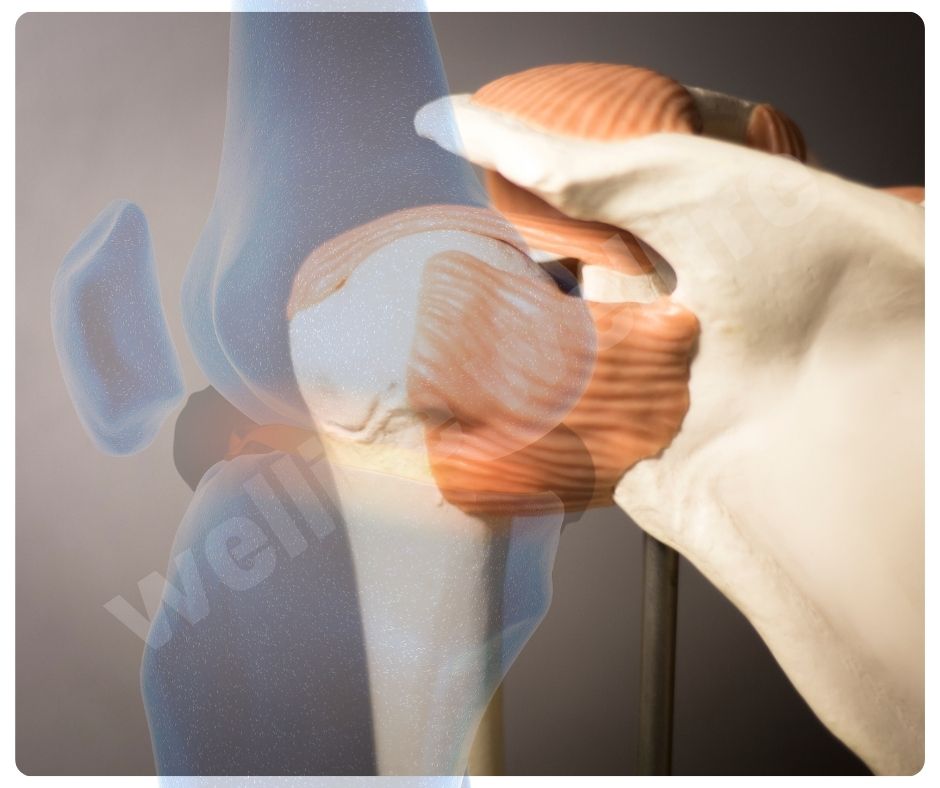

관절 기능 개선

콘드로이친 효능은 관절의 움직임을 부드럽게 하고, 전반적인 관절 기능을 개선하는 데도 효과적입니다. 이는 관절염 환자뿐만 아니라 관절 건강을 유지하고 싶은 모든 사람들에게 유익합니다.

- 관절 윤활: 관절액의 생산을 촉진해 관절의 윤활을 개선하는 효능이 있습니다.

- 관절 유연성 향상: 관절의 유연성을 높여 활동성을 증가시킵니다.